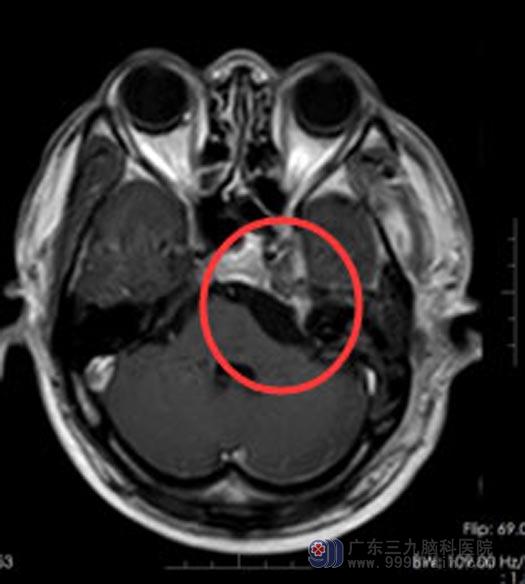

一个月前,症状变得越来越重,不但发作频繁还出现了头晕。后来,听朋友介绍,赵先生来到了广东三九脑科医院综合神经外科。MR结果示:左侧鞍旁至左侧桥小脑角区囊实性占位性病变,考虑三叉神经鞘瘤。

三叉神经起源于脑干,跨越多个颅底孔道,分布范围深在,周围毗邻脑干、海绵窦、颈内动脉及多条颅神经。体积较大的三叉神经鞘瘤,手术很具有挑战性。

在充分的术前准备后,由鲁明副院长为赵先生实施“左侧跨中后颅窝三叉神经鞘瘤切除术”。术中见肿瘤有完整的包膜,丰富的血运,和三叉神经粘连,显微镜下充分保护血管与神经,完整切除了肿瘤。